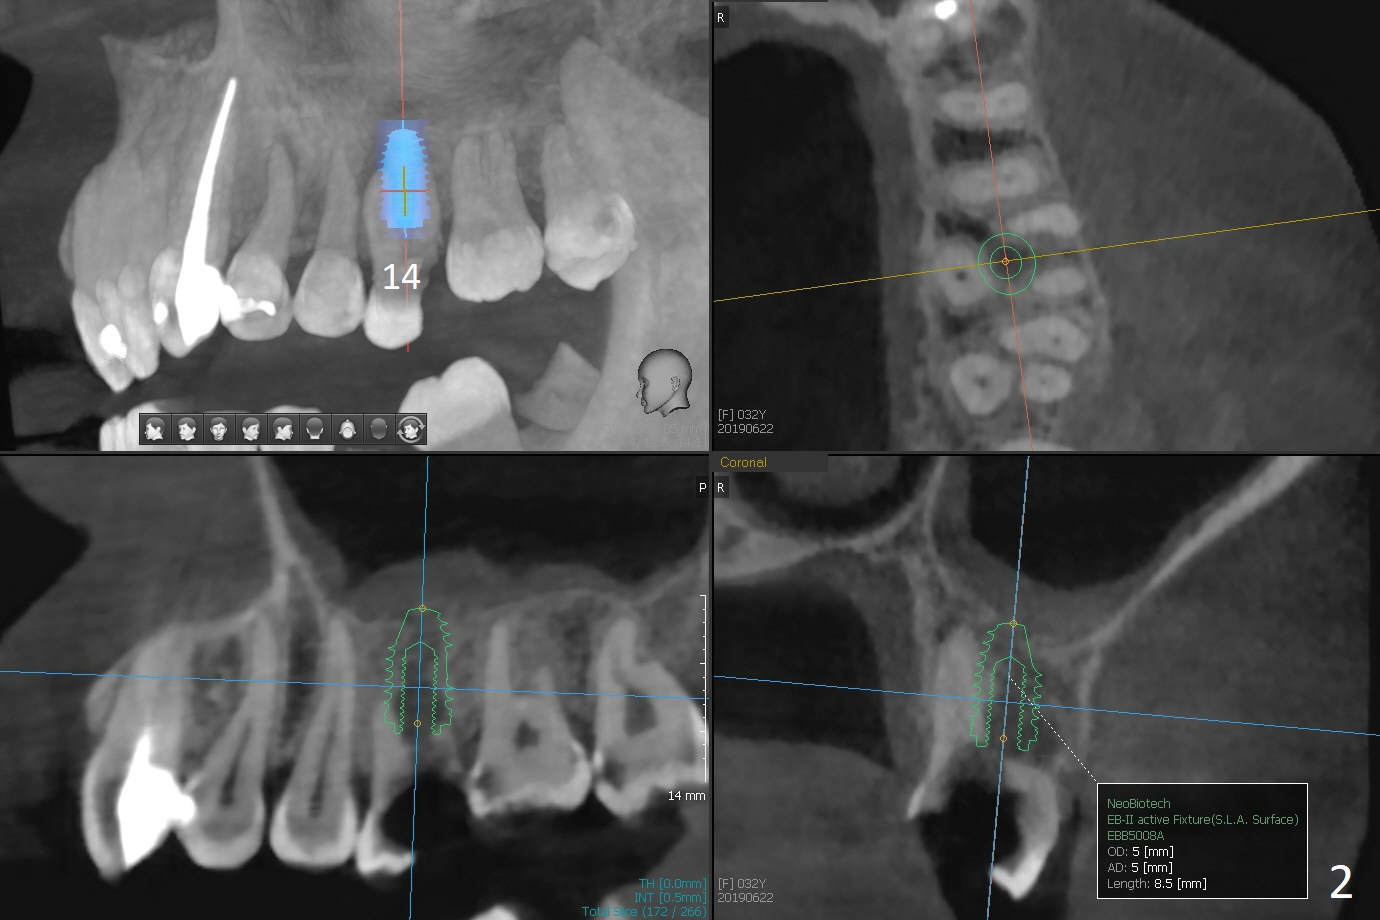

A 32-year-old woman has poor dentition: missing teeth and shifting (Fig.1). The teeth #14 and 19 will be extracted for implants (Fig.2,3 (5x8.5 and 4x11.5 mm)). Draw 2 tubes of blood for PRF. Prepare temporary and healing abutments for 14 and 19, respectively. SRP will be done with #17 extraction.